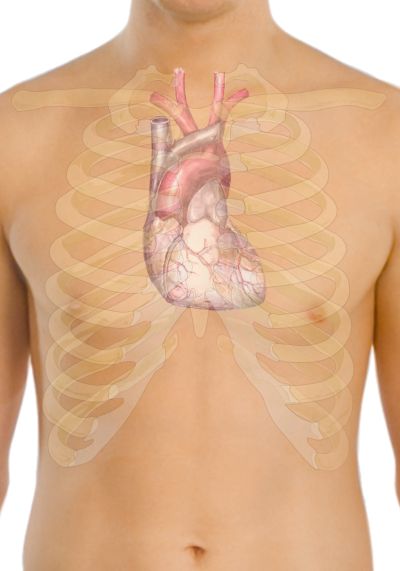

El cor és un òrgan muscular anatòmicament complex, que impulsa la sang a través dels vasos sanguinis del sistema circulatori, la qual proveeix les cèl·lules de l’organisme d’oxigen i nutrients. És l’element central del mediastí, la regió anatòmica compresa entre els dos pulmons.

La forma del cor sembla un con arrodonit de la mida d’un puny, la punta del qual es troba avall i lleugerament a l’esquerra. El cor es troba generalment una mica a l’esquerra, darrere l’estèrnum. Es nota el cor a l’esquerra perquè la seva part esquerra (ventricle esquerre o cor esquerre) és més forta (bomba sang a totes les parts del cos). El pulmó esquerre és més petit que el dret perquè el cor ocupa una major part de l’hemitòrax esquerre.

La demarcació del cor, és a dir, les fronteres que el limiten, és la següent (vegeu la figura):

- Un punt 9 cm a l’esquerra de la línia medioesternal (àpex del cor).

- La setena articulació esternocostal de la dreta.

- La vora superior del tercer cartílag costal dret, a 1 cm de la línia esternal dreta.

- La vora inferior del segon cartílag costal esquerre, a 2,5 cm de la línia esternal lateral esquerra.